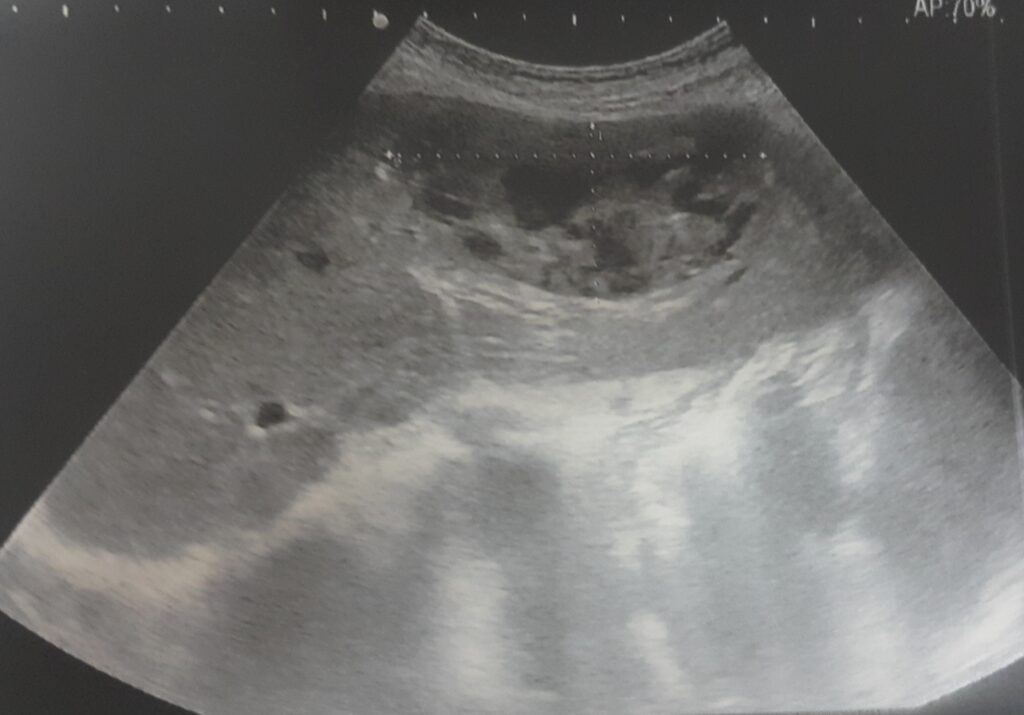

ropień wątroby